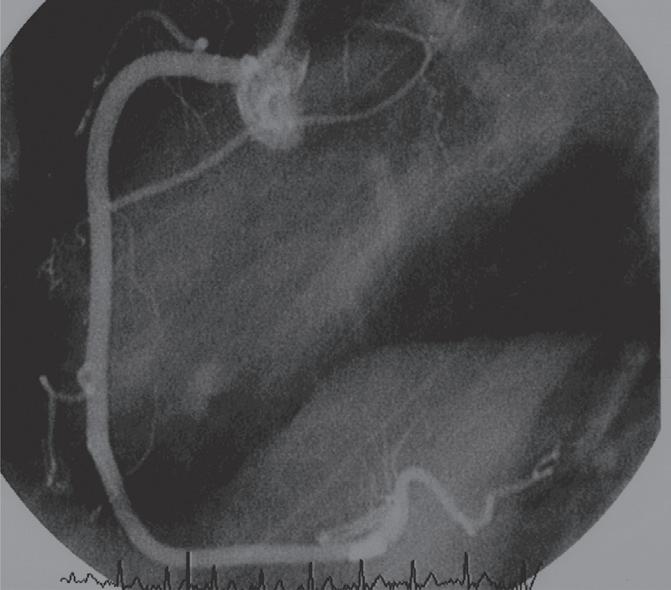

FigurA 3.7 – Angiografia da coronária direita. A e B. Obtida em oblíqua anterior direita (OAD) onde se observa a artéria do nódulo sinusal saindo da porção mais proximal da coronária direita e a artéria do NAV saindo junto à crux cardíaca; C e D . Obtida em OAD caudal onde se observa a artéria do NAV saindo da artéria coronária direita no momento em que dá origem à artéria descendente posterior (crux cardíaca). NS – artéria do nódulo sinusal; NAV – artéria do nódulo auriculoventricular.

NS NAV NS NAV NAV NAV NS NS